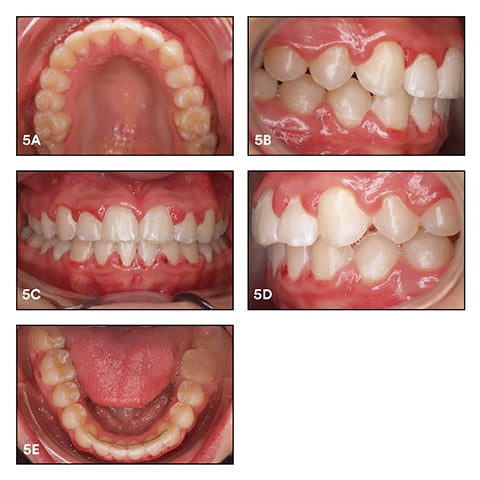

In March 2016, we carried out slight interproximal enamel reduction (stripping) in the mandible to solve Bolten discrepancy and avoid premature contacts in the anterior area. We used a powerchain for gap closure. Figure 5 shows the treatment outcome in June 2016 after bracket removal. Total treatment time was 18 months, and 12 appointments were required. One bracket repair on a lower second premolar (45) was necessary after eight weeks of treatment, so we assume this was not a bonding mistake. For the retention phase, the patient received fixed retainers and a removable orthodontic appliance. At a recall in October 2017, the situation was stable and no relapse had occurred. See Figure 5a-e.